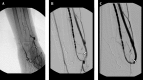

Figure 3.

A 53-year-old man with radiocephalic fistula in the left forearm. He had a previous stent placement in this area. A, AV fistulogram shows the thrombus in the stent that occurred in the third month follow-up (arrow). B, The balloon dilatation (6 mm) is used for the stent expandation and a new 7 mm sized second stent is placed at the same area. The control angiogram images show patency of the vascular access (arrow).